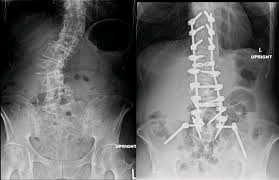

Many people with scoliosis were diagnosed with the condition as children, before undergoing complete skeletal growth. More ...